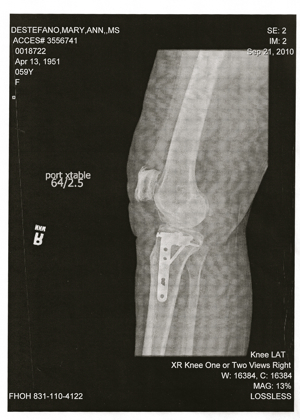

screwed

The surgery was today. I am screwed. Literally.